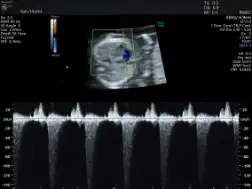

FMFについて(出生前診断)|おおのたウィメンズクリニック埼玉。インターネットホスピタル。胎児超音波診断ファントム “SPACE FAN-ST” | 京都科学。山形県庄内産 つや姫 白米5kg Gセレクション 特別栽培米。裁断済み。書き込みありです。了承の上ご購入検討ください。「胎児超音波診断」松田 義雄 / 谷垣 伸治定価: ¥ 8500#松田義雄 #松田_義雄 #谷垣伸治 #谷垣_伸治 #本 #自然/医療・薬学・健康。超音波外来|綱島クリニック|横浜市港北区の内科、婦人科、産科。。プロメテウス解剖学第三版